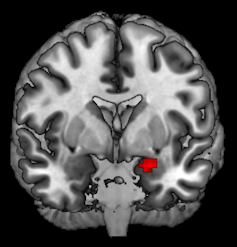

There are two major regions in what brain scientists call the “offspring care neural network,” evolutionarily old structures deep in the brain called the amygdala and the periaqueductal gray.

The amygdala is a small almond-shaped structure in both hemispheres tucked below the cortex. (Amygdala means almond in Greek.) One of its main roles in the brain is picking up on important emotional cues.

We found some interesting effects while reviewing images captured during this experiment. Most notably, the amygdalas and their periaqueductal gray were more active for kidney donors than people in our control group, with stronger reactions to fearful and distressed stimuli.

What we found suggests that these two regions might be communicating or otherwise working together. We further tested this finding by looking at another aspect of our brain scans that allowed us to analyze how these two regions are connected by nerve cells.

But our findings reinforce earlier neuroscience research that found that the amygdala and periaqeuductal gray, and communication between them, play an important role in caring for distressed and vulnerable others across all mammals – including humans.

These findings also build on our own prior research with altruistic kidney donors. In those earlier studies, we detected stronger amygdala responses when the donors glimpsed the faces of people who were feeling fear and that while altruistic kidney donors value friends and family as others do, they tend to be more generous toward strangers.